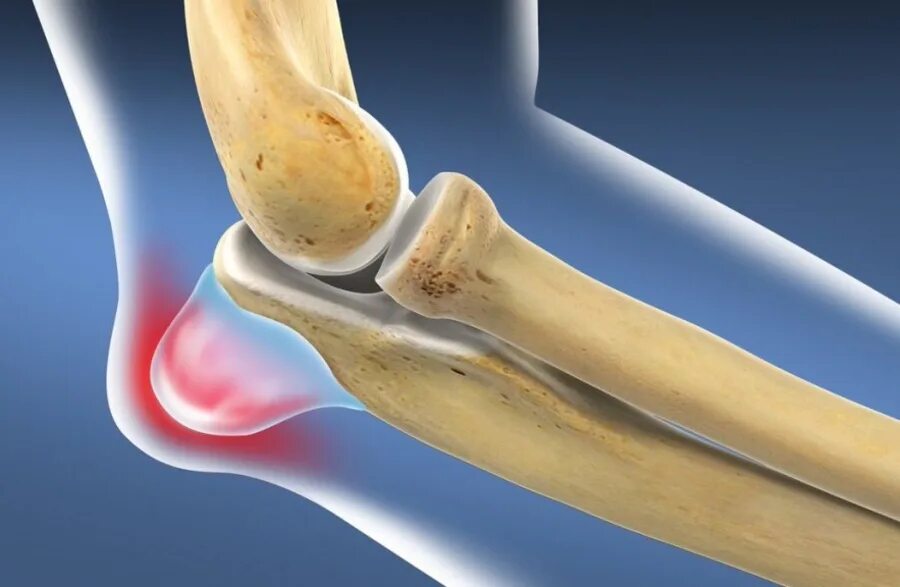

Артроз пяточных суставов